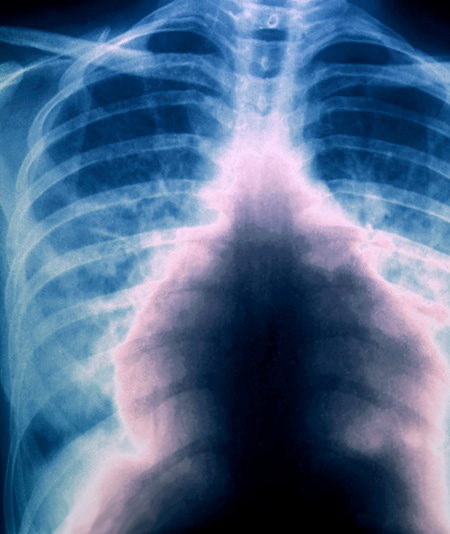

Røntgen thorax viser massiv lungeembolisme. Foto: Science Photo Library